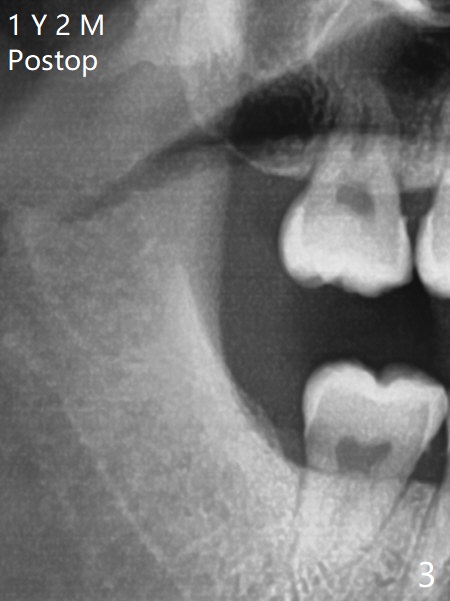

A 19-year-old man with mental retardation returns to clinic for extraction of the 3rd molars in 2 visits (Fig.1,2). The sockets heal without delay (Fig.3,4).